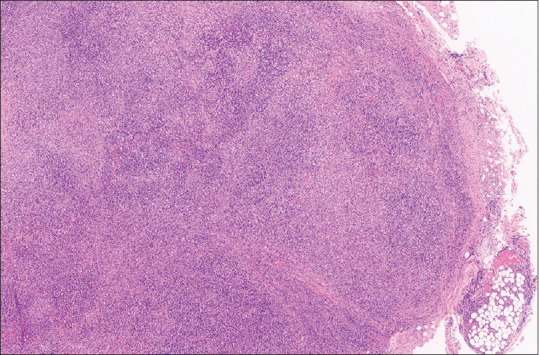

Abstract: Cervical lymphadenopathy can be due to numerous causes. The common causes include reactive and infections conditions in children and malignancy in the elderly. Kikuchi-Fujimoto disease (KFD) is a rare cause of cervical lymphadenopathy. As viral vaccines contain viral antigens, they can trigger the development of KFD. The human papillomavirus (HPV) vaccine can trigger KFD. It is important to elicit a history of prior vaccination to identify the trigger in patients with necrotising histiocytic lymphadenitis suspected of having KFD. We hereby report a case of a 16-year-old female who was diagnosed with HPV vaccine induced KFD. Ours is the first case to be reported from India. Histopathology revealed necrotising histiocytic lymphoid hyperplasia and the absence of neutrophils, eosinophils, plasma cells, vessel wall vasculitis, haematoxylin bodies, and Reed-Sternberg cells, and negative aerobic, MTB cultures, anti-nuclear antibodies, clinched the diagnosis of KFD.

Abstract Image